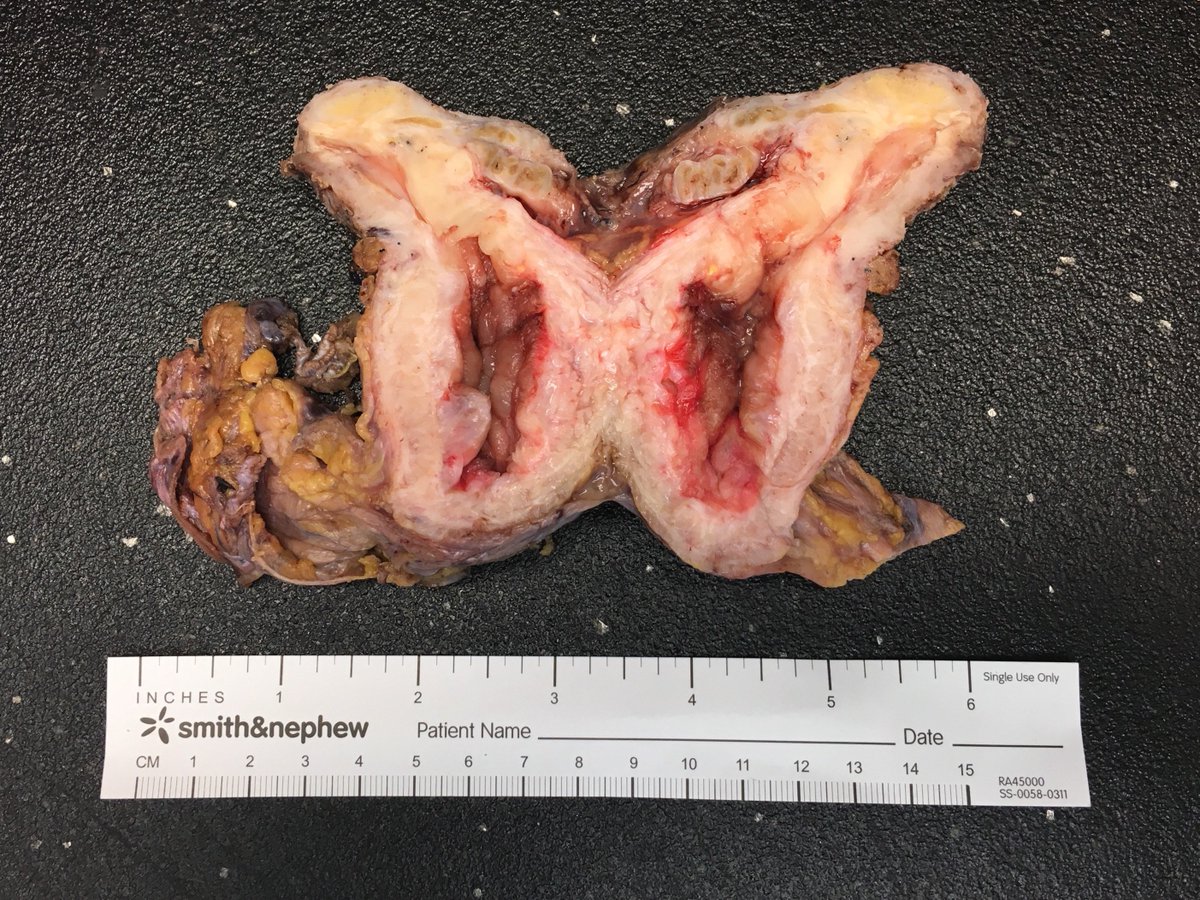

The most beautiful gout picture I have ever seen! From Theresa Smith of #SoMeDocs (lucky picture from a new scope and polarizer on embedded tissue). Ten important facts about gout here: creakyjoints.org/treatment/teng… #pathart The Pathologist Human Pathology